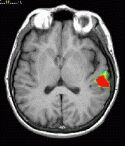

Transverse fMRI image

T1 weighted MRI

Transverse image at the level of the planum temporale. The left hemisphere is seen in the right side (radiological convention). The subject's task was listening to a story.

The red bubble seen on the left side corresponds to areas related to complex semantic processing.